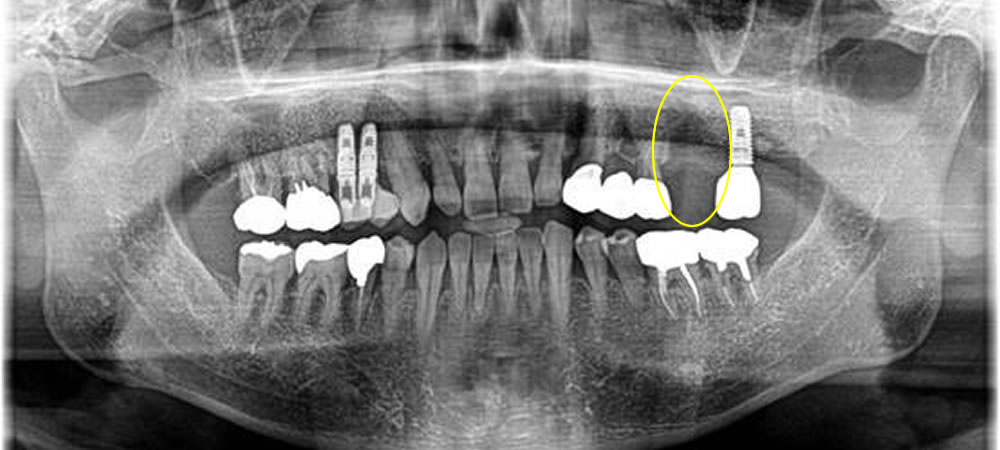

こちらの患者さまは、歯周病により左上第一大臼歯を抜歯され、咬み合わせの回復にインプラント治療を選択されました。

歯周病により歯を支えている骨の損傷が大きかったため骨造成(骨を増やす処置)も追加で行いました。

治療後はレントゲンでも確認できるように骨もしっかりとできています。今では固いものも噛めるようになり、大変満足いただけました!